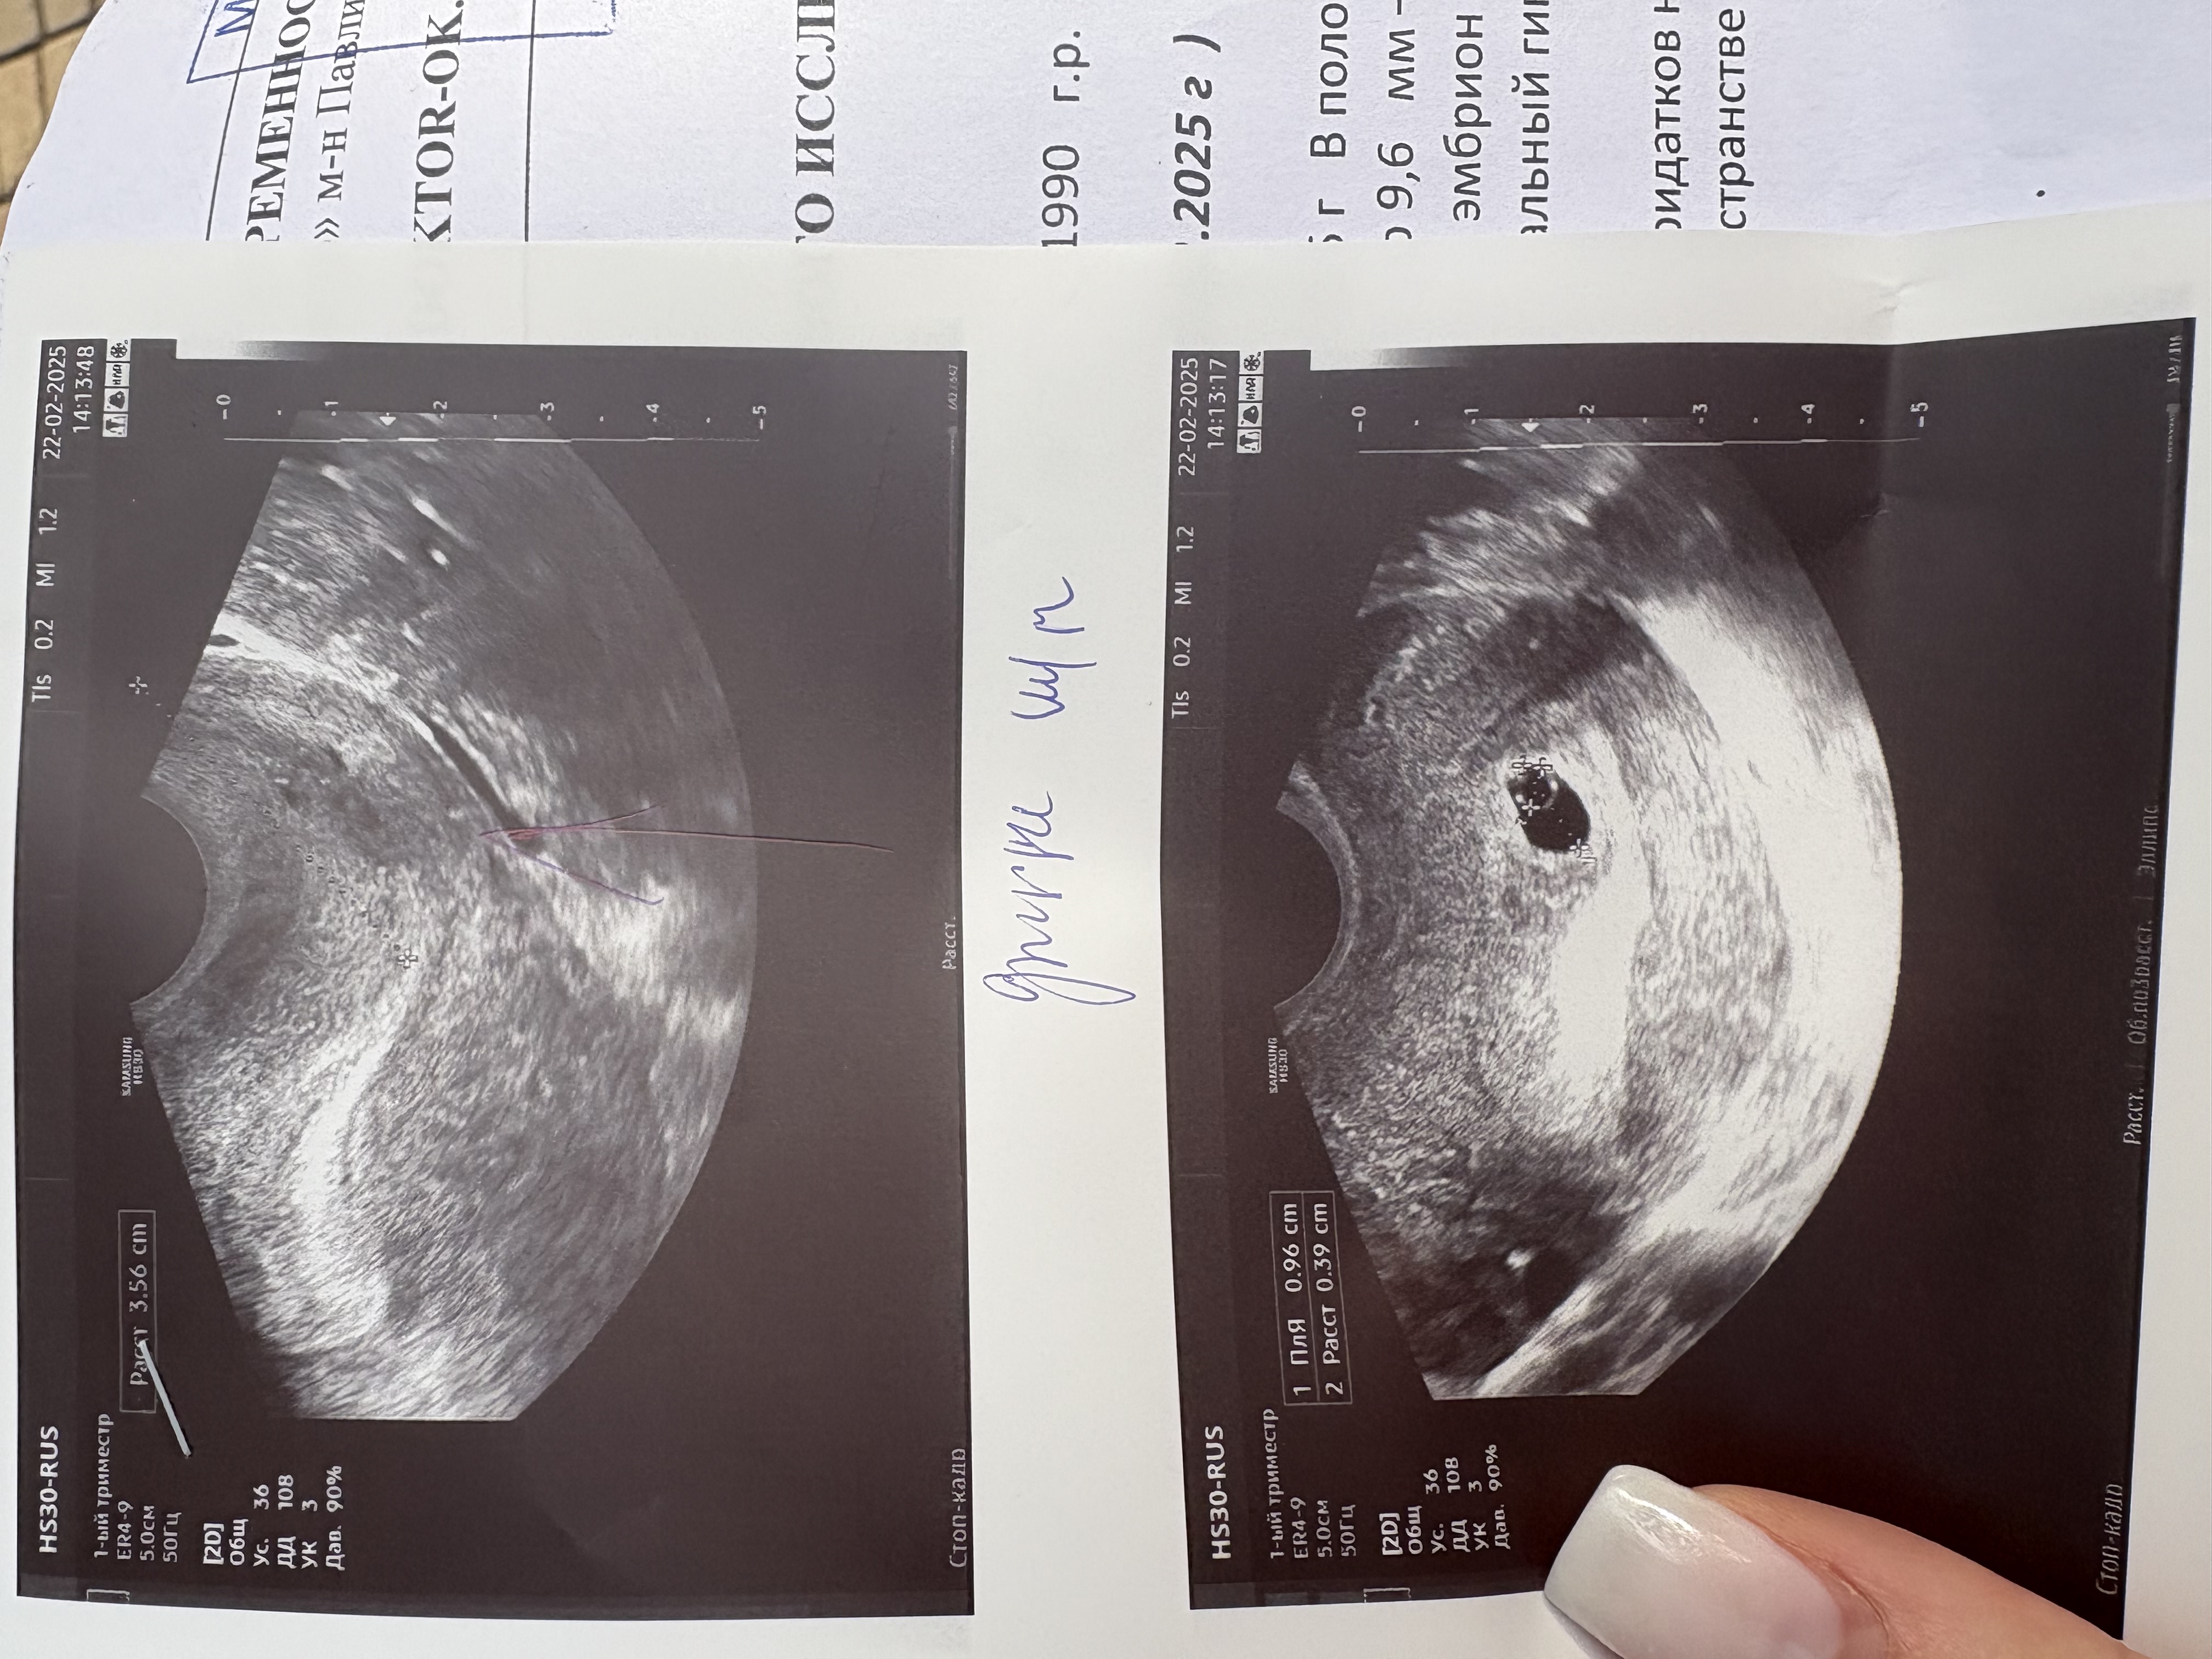

33 дпп или срок 7нед и 3 дня Узи 17 дпп